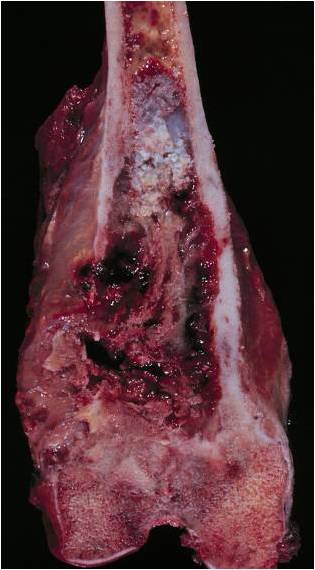

Gross Pathology

- Areas with typical lobular, blue-gray myxoid hyaline cartilage tissue

- Or overtly cartilaginous appearance of mature hyaline cartilage

- Zones of brown, tan, or hemorrhagic tissue

- Lacking the consistency of cartilage

- Dedifferentiated component may only be a minor portion of the overall tumor

- May also be so extensive that little cartilage is recognizable